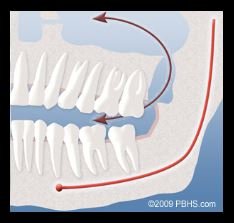

我有三颗阻生牙。其中左下是completely bony,被困在牙龈和颚骨之间,进食后非常容易有残余塞在牙龈和牙齿的缝隙,导致疼痛。左上和右下是Mesial impaction,内侧向阻碍,左上比较严重的是很有可能一直在磨损我做过牙髓治疗的大牙(没来得及做牙冠)。右上是最简单的智齿,但是比大牙偏长,拔完下面的智齿后,向下咬合时上面的智齿会容易咬到牙龈。

其次是神经损伤,也是牙医强调的。拔除下排阻生牙时,切割下颌骨时,有可能损伤神经,暂时的或永久的。由于下颌骨内有一根神经为下巴、下唇提供感觉,该神经通常离智齿根部很近,但在青年时期,牙根不会很长,离神经较远。但在25岁之后,神经损伤的风险会增加。也就是我。。。。